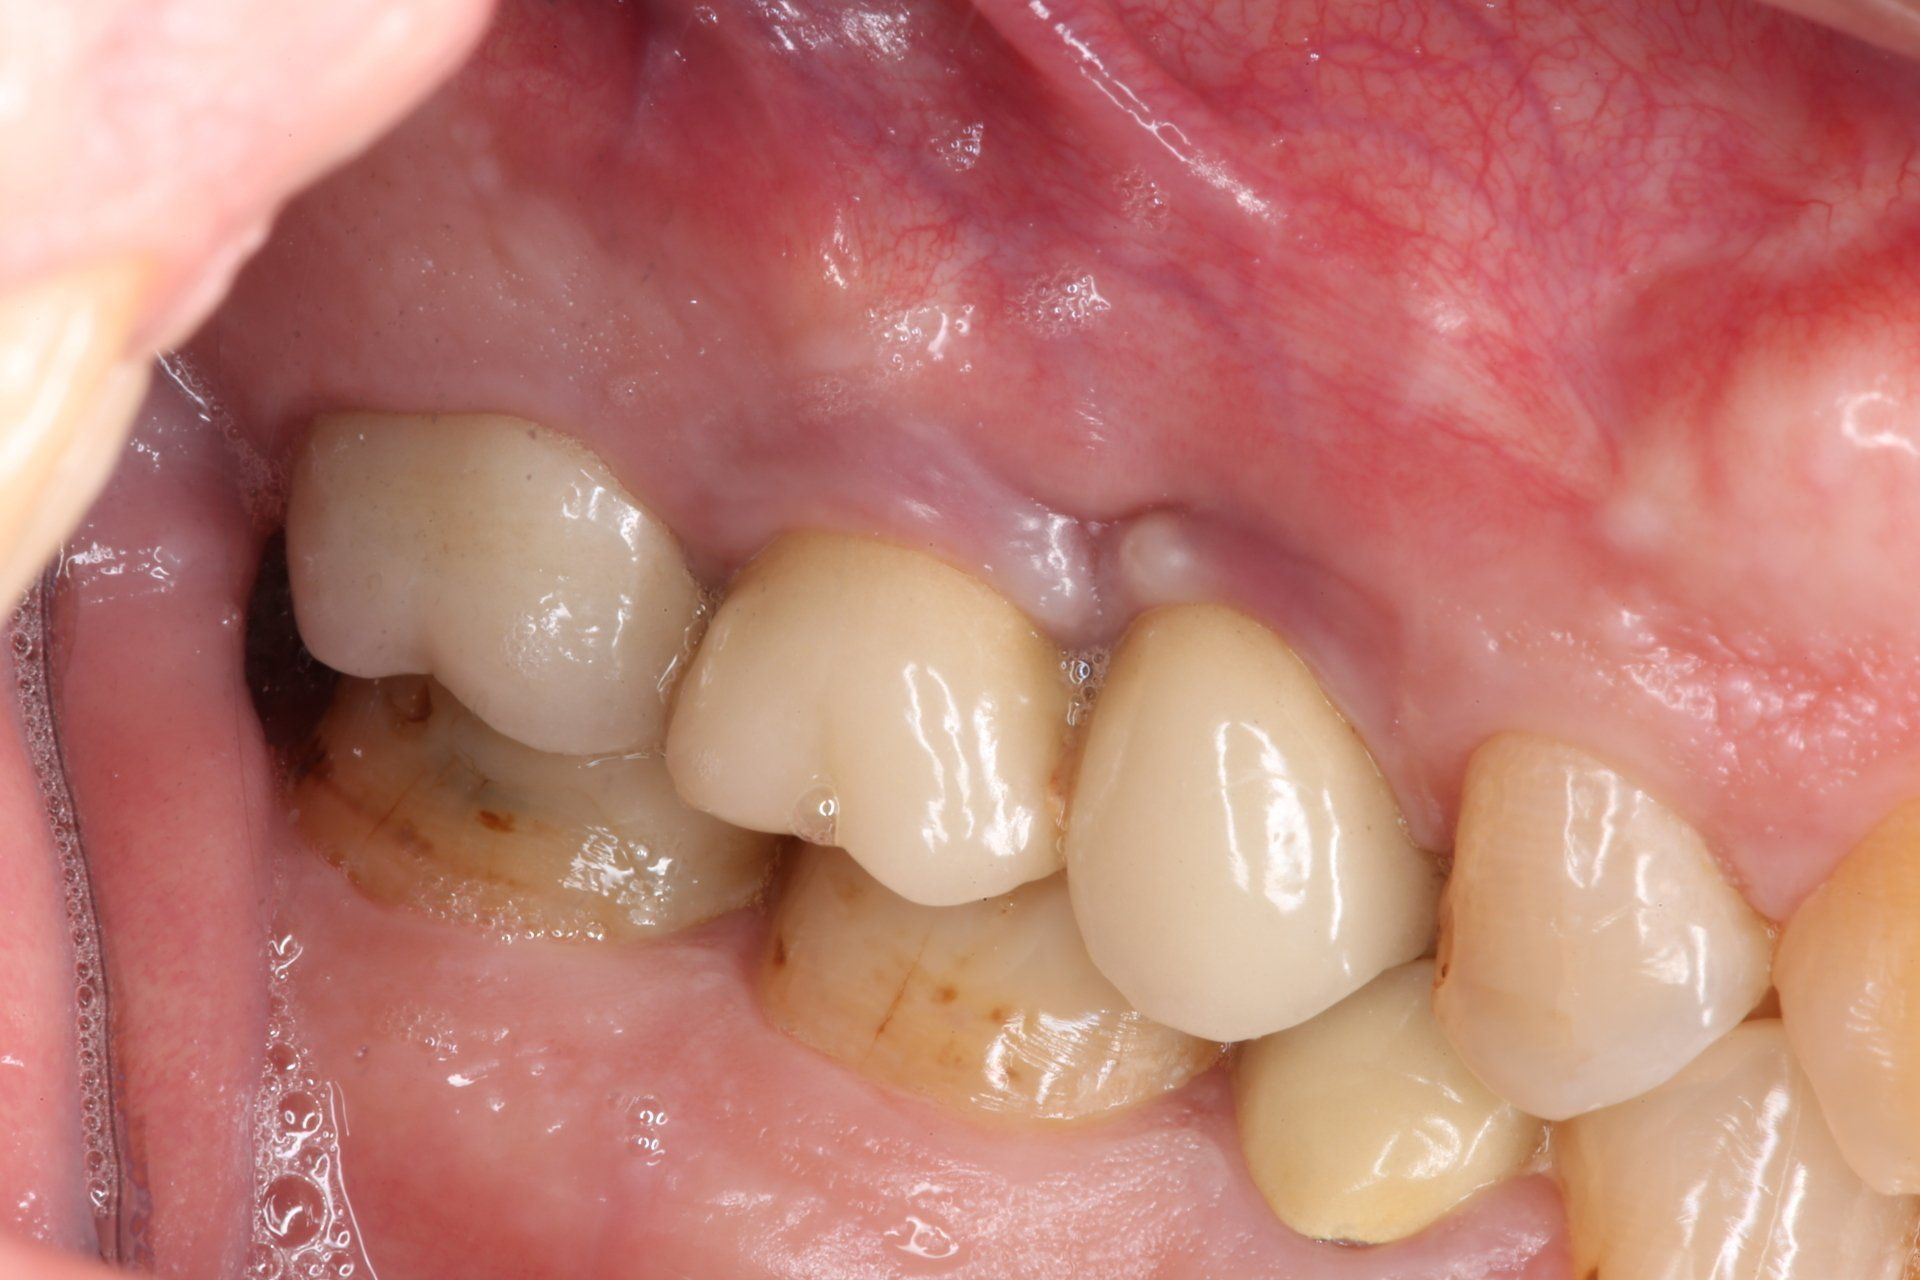

Dopo dieci giorni (T1) di utilizzo di PerioTabs®, si è notato un miglioramento dal punto di vista clinico (Fig. 8 e 9). Il P.I. è sceso al 57%, il BoP al 26% e sono diminuite anche le profondità di sondaggio (Fig. 10).

#dida Fig. 9.1 e 9.2: Foto laterale zona 2.5-2.6 a T1 prima e dopo il sondaggio

Il risultato estetico e l’aspetto clinico della salute tissutale è evidente a T2 (Fig. 11 e 12). Da notare un ulteriore miglioramento del P.I. sceso al 12% e del BoP diminuito al 2% (Fig. 13) dopo un'aggiuntiva istruzione e motivazione all’igiene orale domiciliare con l’uso dello spazzolino.

#dida Fig. 12: Foto dettaglio zona 2.5 e 2.6 a T2

Dopo novanta giorni (T3) si evidenzia una situazione di stabilità (Fig. 14, 15 e 16). Il P.I. corrisponde all’ 8% e il BoP all’1% (Fig. 17).

#dida Fig. 15: Foto dettaglio zona 2.5 e 2.6 a T3